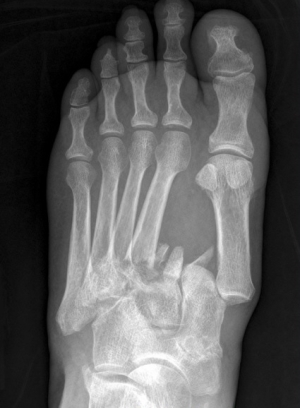

Диагностировать травмирование можно только при рентгенисследовании, выполненном в классических и косой проекциях.

Вывих в суставе Лисфранка наблюдается крайне редко, зачастую он комбинируется с переломом.

Переломовывих подобной локализации занимает около 2% от общего числа травм рук и ног и 29% среди вывихов стопы. В практической медицине они отмечаются часто, но из-за неверного диагностирования их относят в группу редко наблюдаемых.

В основном эта травма сочетается с повреждением целостности костных образований плюсны,смещенных латерально, медиально, в подошвенном или тыльном направлении. Иногда имеют место дивергирующие переломовывихи с дистанцированием костных образований плюсны в противоположные направления (расходящиеся).